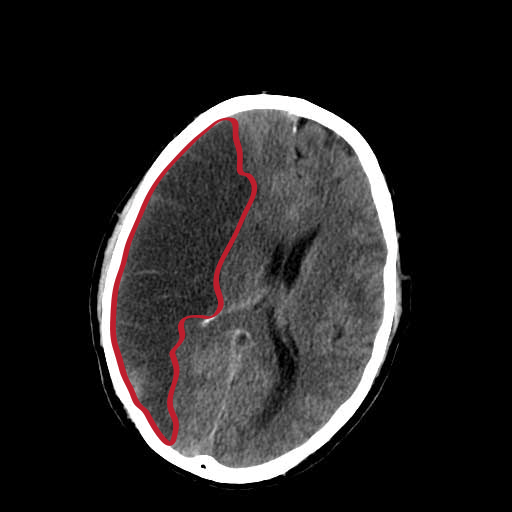

Systemic emboli travel through the blood stream and lodge in the smaller branches of arteries. The sudden occlusion of the artery and disruption of blood flow can cause ischaemia or infarction of the area supplied. For example, in a stroke, the emboli may travel from a detached mural thrombus in the cardiac chamber, or a thrombus from an atherosclerotic plaque in the carotid artery, to the cerebral artery causing cerebral infarction.